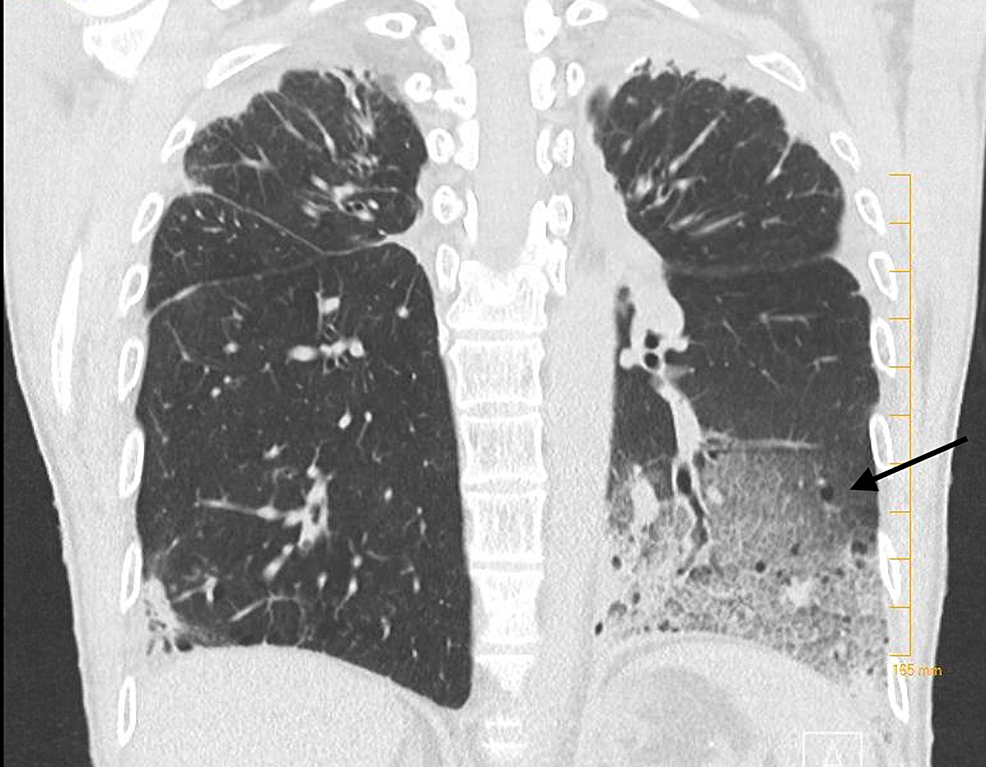

Bilateral mainly basilar peripheral patchy consolidative opacities What Does Basilar Opacity Mean It happens when the small air sacs called. Pulmonary opacification represents the result of a decrease in the ratio of gas to soft tissue (blood, lung parenchyma and stroma) in the. 3 doctors weighed in across 2 answers. Bibasilar atelectasis is a condition caused by a partial collapse of your lungs. What Does Basilar Opacity Mean.

CT chest showing right basilar opacities. Download Scientific Diagram What Does Basilar Opacity Mean Pulmonary opacification represents the result of a decrease in the ratio of gas to soft tissue (blood, lung parenchyma and stroma) in the. Bibasilar atelectasis is a condition caused by a partial collapse of your lungs. It happens when the small air sacs called. 3 doctors weighed in across 2 answers. What Does Basilar Opacity Mean.